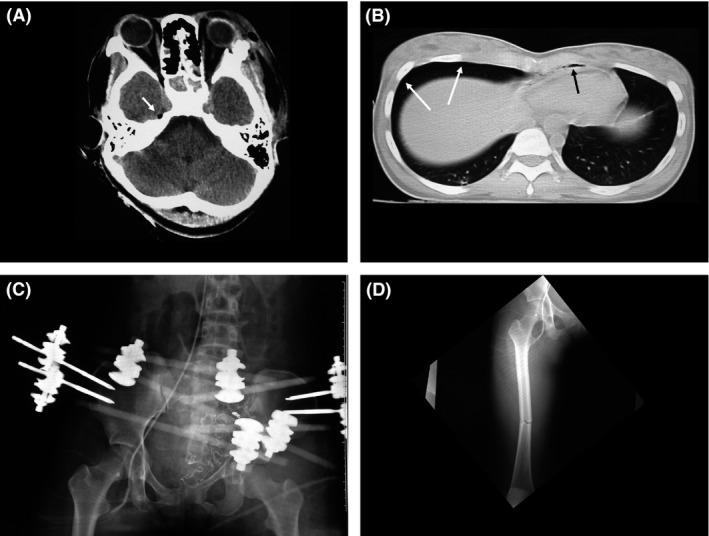

A 22-year-old woman attempted a suicidal fall after using a knife to stab herself. She was transported to a local hospital. A radiological study revealed fractures to the patient's face and the base of her skull, pneumocephalus, traumatic subarachnoid hemorrhage, stab wounds to the neck and chest, pneumothorax, unstable pelvic fracture, and right femoral shaft fracture. Her circulation status became unstable. We sent medical staff members to the local hospital by doctor helicopter. The patient underwent tracheal intubation and the insertion of a chest drain, and was evacuated by doctor helicopter. After aggressive intensive treatments in our hospital, the patient finally obtained social rehabilitation.

一名22岁女性在持刀自残后试图跳楼。她被送往当地医院。影像学检查显示患者面部和颅底骨折、气颅、创伤性蛛网膜下腔出血、颈部和胸部刺伤、气胸、不稳定骨盆骨折以及右股骨干骨折。她的循环状况变得不稳定。我们通过医生直升机将医务人员送往当地医院。患者接受了气管插管和胸腔引流管插入,随后通过医生直升机转运。在我院进行积极的强化治疗后,患者最终实现了社会康复。